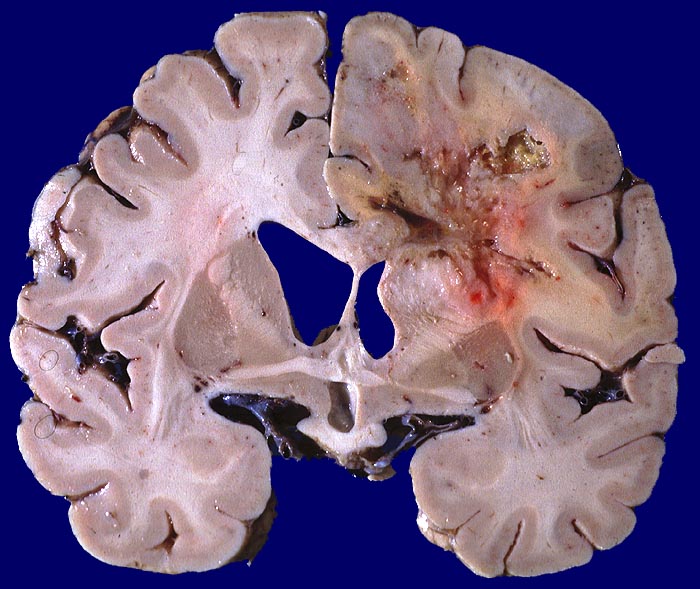

Lokalisation:

Bevorzugte Lokalisationen sind das Marklager des Frontal- und Temporallappens. Glioblastome des Hirnstammes sind selten und betreffen meist Kinder. Von dort breiten sie sich oft über den Balken schmetterlingsförmig auf die Gegenseite aus. Weniger als 5% der Tumoren wachsen multizentrisch. Eine Aussaat in den Subarachnoidalraum mit Metastasierung über den Liquor findet sich selten. Noch rarer sind hämatogene Metastasen in extraneurale Organe.

Morphologie:

Die Schnittfläche ist auffallend bunt. Dies ist bedingt durch ein Nebeneinander von graurotem vitalem Tumorgewebe, gelben Nekrosen, roten Einblutungen und gelegentlich grünlichen Gallertzysten.